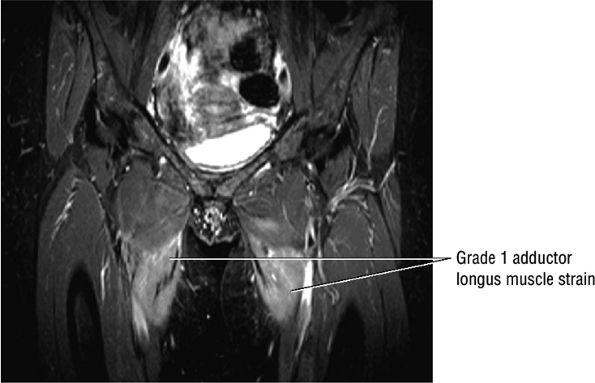

Grade 1: Minimal disruption of the musculotendinous junction (Fig. 3.106). Clinically, a grade 1 strain may simply result in a muscle spasm or cramp.

Grade 2: A partial tear with some intact musculotendinous fibers (Fig. 3.107). Clinically, there is discomfort during sports activity or training, but it usually resolves with rest.

FIGURE 3.106 ● Bilateral adductor longus grade 1 muscle strain with diffuse hyperintense muscle edema. Coronal FS PD FSE image.